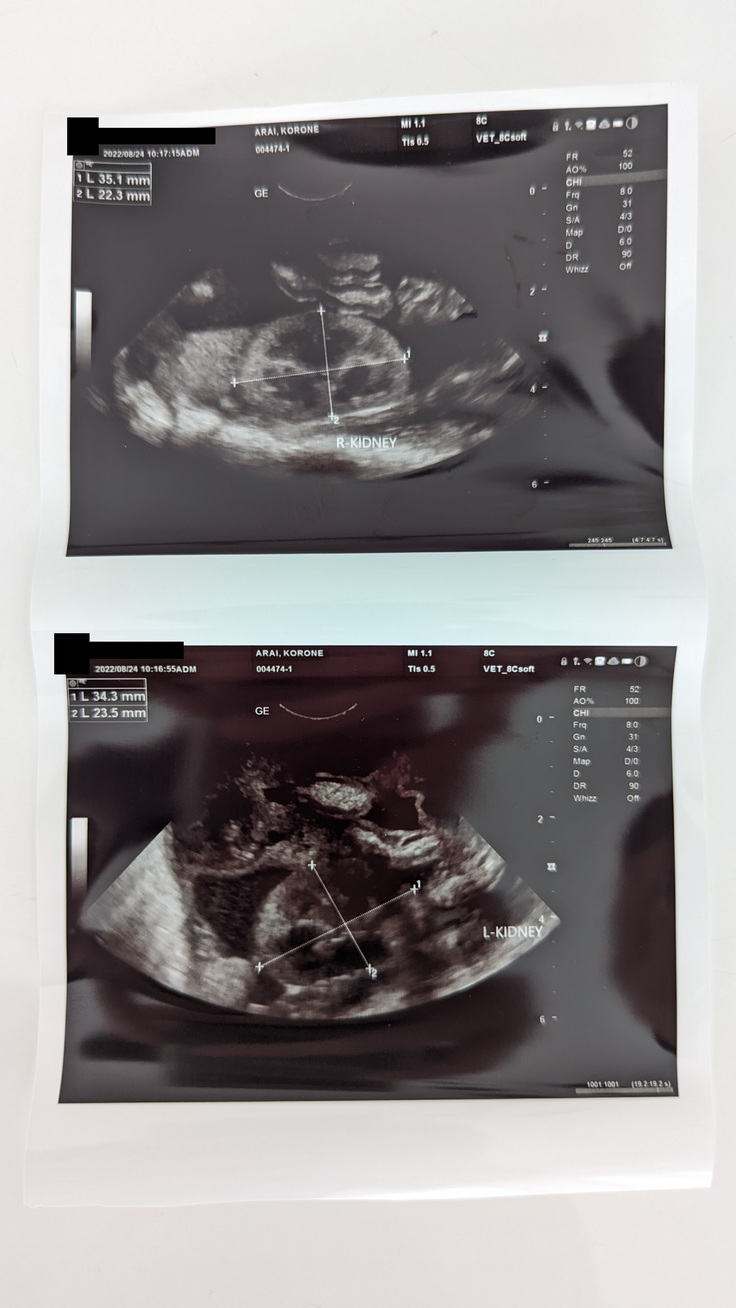

2022年08月24日別の病院で診察頂いた結果、やはりFIPの可能性が高いとのことで仮診断を頂き、既に試薬による治療を開始しています。

こちらはエコー写真です。腹水に浮いた内臓が見えます。

現在では、下腹部あたりに腹水が溜まっており、膨らんでいます。